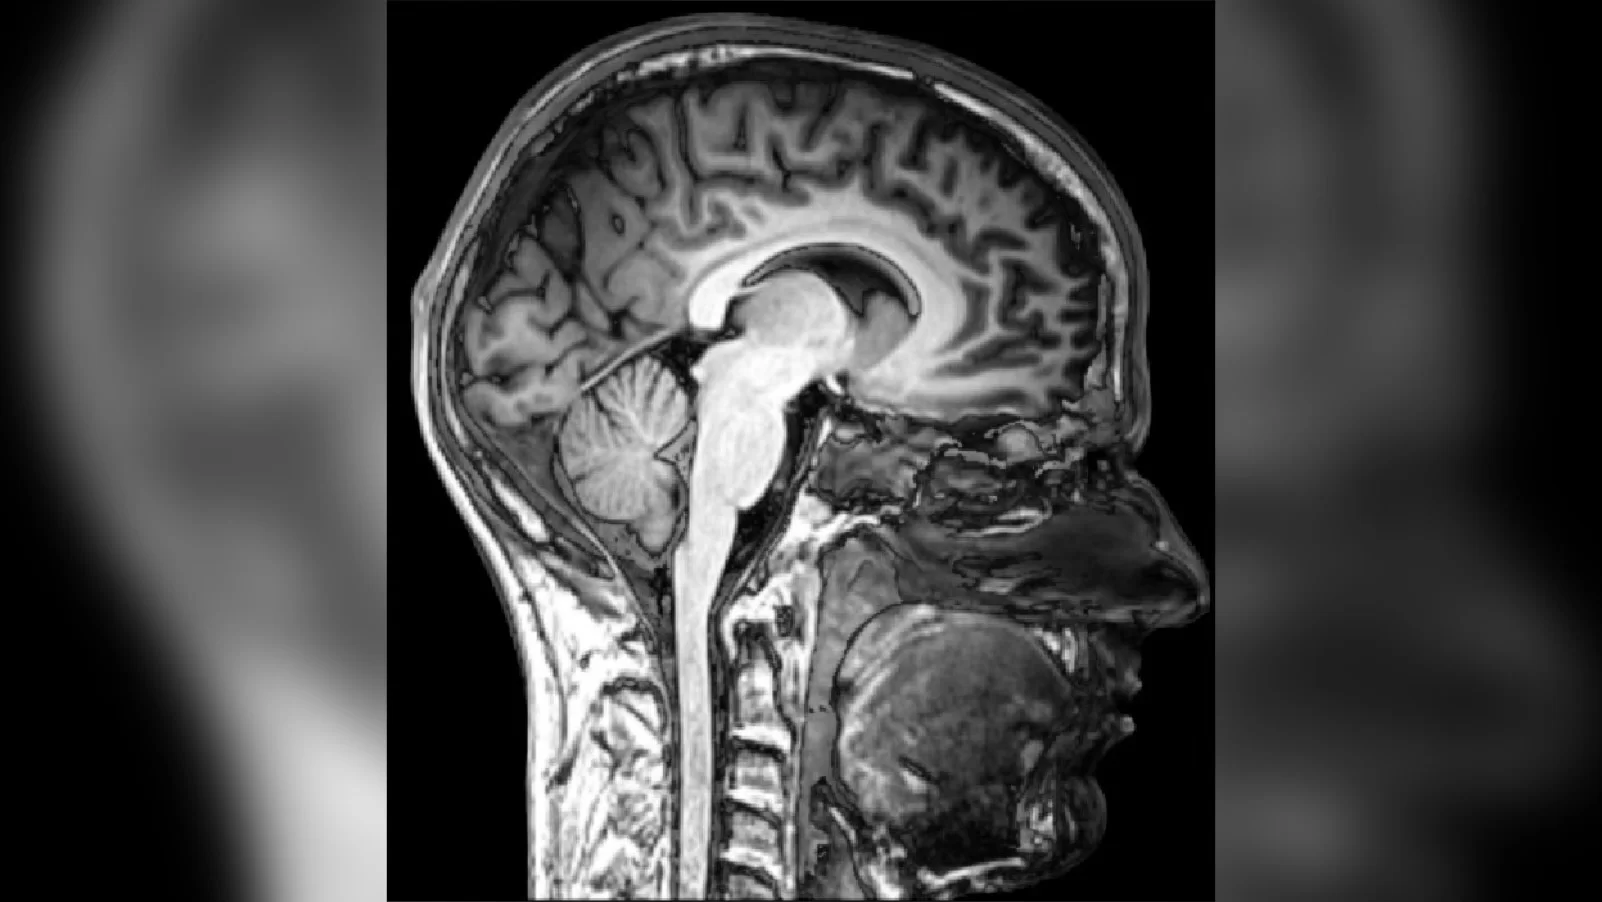

Любовь к «мясу с кровью» тоже требует пересмотра, но механизм здесь хитрее. 52-летний американец страдал от мигреней, которые не брали таблетки. МРТ показало: его мозг был нашпигован кистами — нейроцистицеркоз.

Как это случилось? Любовь к недожаренному бекону подарила ему взрослого червя в кишечнике (тениоз). Тот начал откладывать яйца. Небрежно помытые руки после туалета замкнули круг: мужчина заразил сам себя, проглотив яйца собственного паразита. Именно они прорвали оборону кишечника и ушли в мозг. В России похожая трагедия на племзаводе «Юбилейный» унесла жизнь 27-летнего парня. Он ухаживал за свиньями и пренебрегал гигиеной, что стало фатальным.

МРТ головного мозга 52-летнего американца